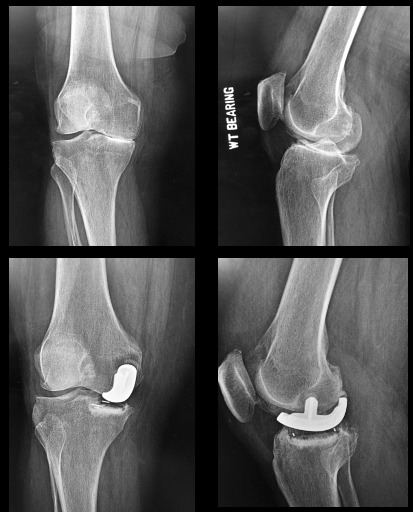

A resection UKA requires a flat saw cut of the tibia and chamfer cuts of the distal femur. A resurfacing UKA utilizes high speed burrs and rasps to remove minimal bone or “patch” the surface of the femur and create a pocket in the surface of the tibial plateau for containing an all-poly wafer-surface inlaid. (Figure 2)

NOTE: Both tibial and femoral bone cuts remove the native surface reference points and knee balancing requires subjective “feel” or robotic references (fit the patient to the component). (Figure 3)

The patient’s pre-diseased joint line is restored which optimizes their natural ligament tension and joint alignment (fit the component to the patient). (Figures 3, 9-10)